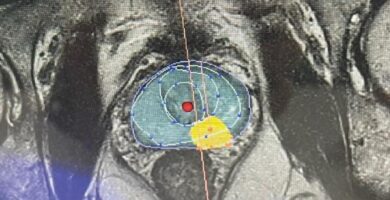

¿Cómo tratar el cáncer más frecuente en el hombre manteniendo su calidad de vida intacta?

Hoy os dejamos un pequeño resumen del publireportaje publicado en La Vanguardia el 8 de Abril sobre la terapia focal en el cáncer de pr...